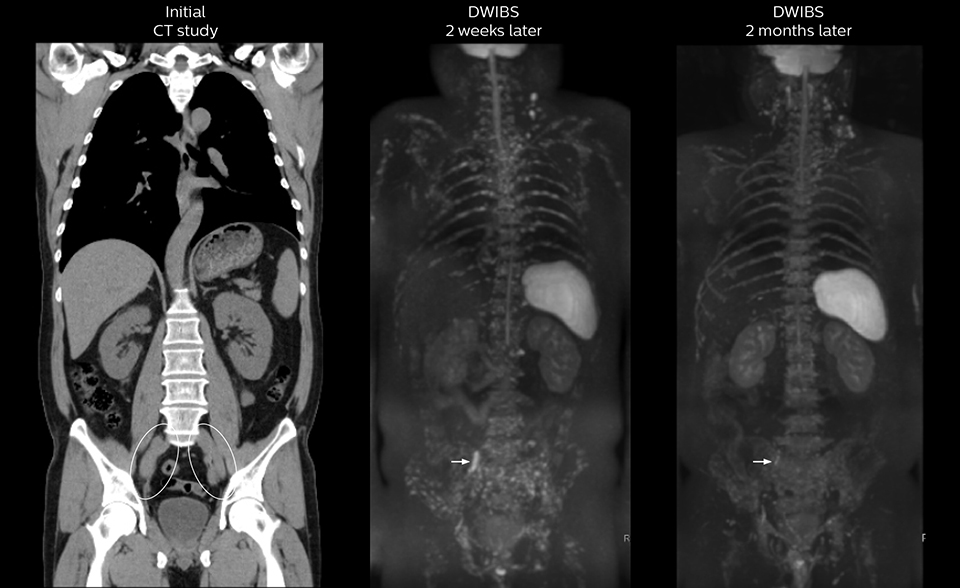

Radiologist Hiroshi Nobusawa, MD, PhD, explains that the coronal DWIBS protocol for whole body DWI is excellent for visualizing lesions in oncology patients. “About 90% of the DWIBS exams are done in this type of patients. The remainder of DWIBS exams are performed to gain information in cases of fevers of unknown origin,” he says.

“The DWIBS sequence’s value in oncology cases is due to the high contrast it creates between lesions and surrounding tissue. Whole body DWI is requested by physicians who need to clarify TNM staging or determine therapeutic strategies, oncologists in need of diagnosis or follow-up scans, surgeons who need to see the presence of distant lesions that are sometimes difficult to detect by CT before surgery, and urologists for the evaluation of bone lesions, and the effect of chemotherapy and radiotherapy.”

Kawasaki Sawai Hospital’s whole body protocol also includes an mDIXON FFE sequence. Because mDIXON provides images for four contrast types – water only, fat only, in-phase and out-of-phase – from a single acquisition, it is useful in many ways.

“mDIXON FFE allows us to quickly get information we need to assess the presence of fat. That gives us more information when we need to diagnose bone lesions, and when we are asked to judge fat-containing lesions such as hepatocellular or renal carcinoma,” Dr. Nobusawa says.

“The mDIXON fat images can help us to differentiate fatty bone marrow from bone lesions. This is especially useful in elderly people, who tend to have fattier bone marrow. The water images provide a high signal-to-noise ratio in the intestinal canal, which is valuable for visualizing lesions in the colon,” he says.

“In-phase and out-phase sagittal T1-weighted FFE images help us to visualize and further characterize bone lesions such as metastasis and bone-marrow hyperplasia that have high signal on DWI. These images are also used throughout radiotherapy, to monitor changes in the fatty bone marrow.”